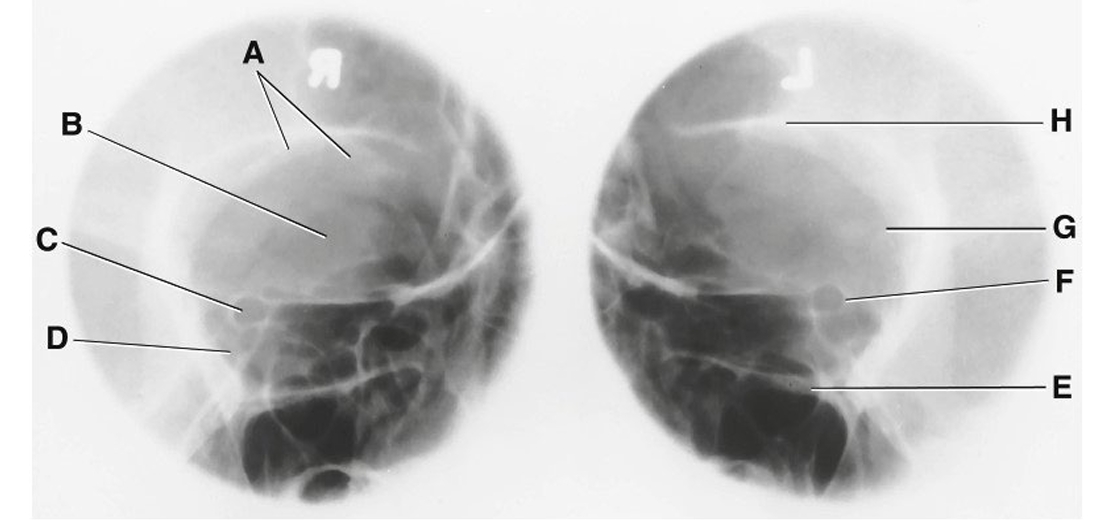

What is A?

Orbital plate of Frontal bone

What is B?

Sphenoid Bone

What is C?

optic foramen and canal

What is D?

Superior Orbital Fissure

What is E?

Infraorbital Margin (IOM)

What is F?

Sphenoid strut

What is G?

Lateral Orbital Margin

What is H?

Supraorbital Margin (SOM)